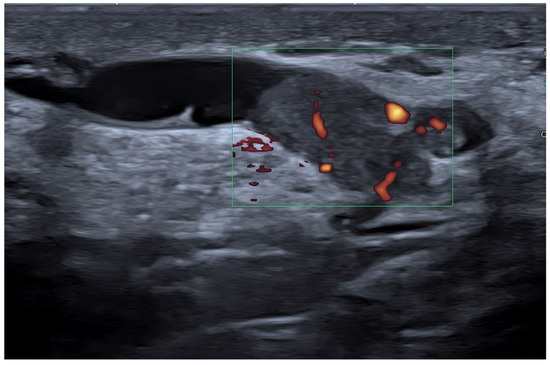

Figure 1. Breast invasive ductal carcinoma. Vascularization as assessed with power Doppler (left) and with MV-Flow (right). Recently developed techniques such as MV-Flow are more sensitive to slow flows and offer a better display of tumor vessels.

Cancer growth is based on neoangiogenesis, i.e., the tumor-induced development of a vascular network. Detecting these flow signals and assessing their characteristics in terms of number, distribution, and appearance are consequently of paramount importance in tumor characterization and monitorization [12,13,14,15,16,17,18,19,20,21,22,23,24,25,26,27,28]. Even if appropriately set to identify small, low-flow vessels, conventional Doppler techniques, including color Doppler and power Doppler, have a limited sensitivity. In recent years, almost all companies have developed filtered techniques capable of working at a higher frame rate and consequently detecting tiny intra- and peri-tumoral flow signals. With these new software facilities, the background and tissue motion artefacts are suppressed and US sensitivity, spatial resolution, and temporal resolution are significantly improved [29,30,31,32,33,34,35,36,37,38]. Some companies have also developed systems capable of quantifying the number of colored pixels within the box, thus quantifying the flow intensity [39]. If a new microvascular tool is available on the scanner, we encourage users to refrain from still using conventional Doppler modalities for breast imaging and to employ more advanced techniques (Figure 1).